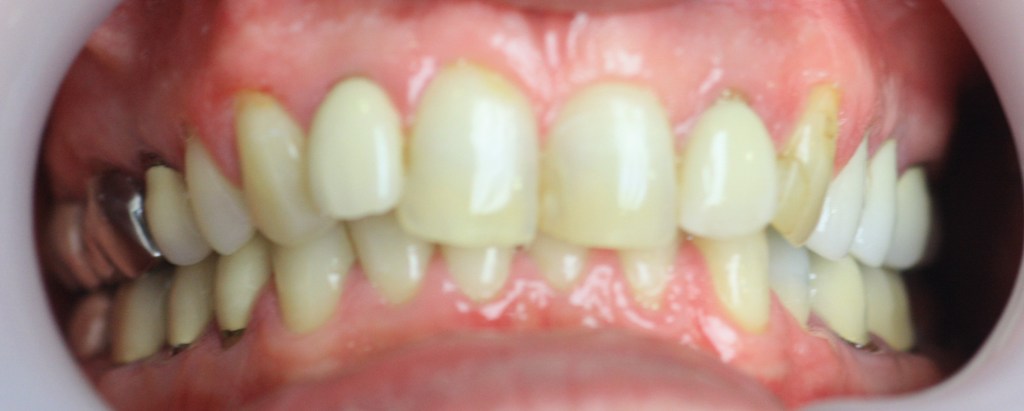

Funkcionális és esztétikai kezelés: harapás korrigálása a fogív kiegyenesítése, fogak közötti rések szűkítése, kereszt harapás megszüntetése az összes megmaradt fog koronázásával. A hiányzó hátsó fogak pótlása implantátumokon megtámasztott koronákkal.

Protetikai munka elkészülésének ideje: 10 munkanap

Koronák anyaga: fémkerámia

Fogszín: A1.